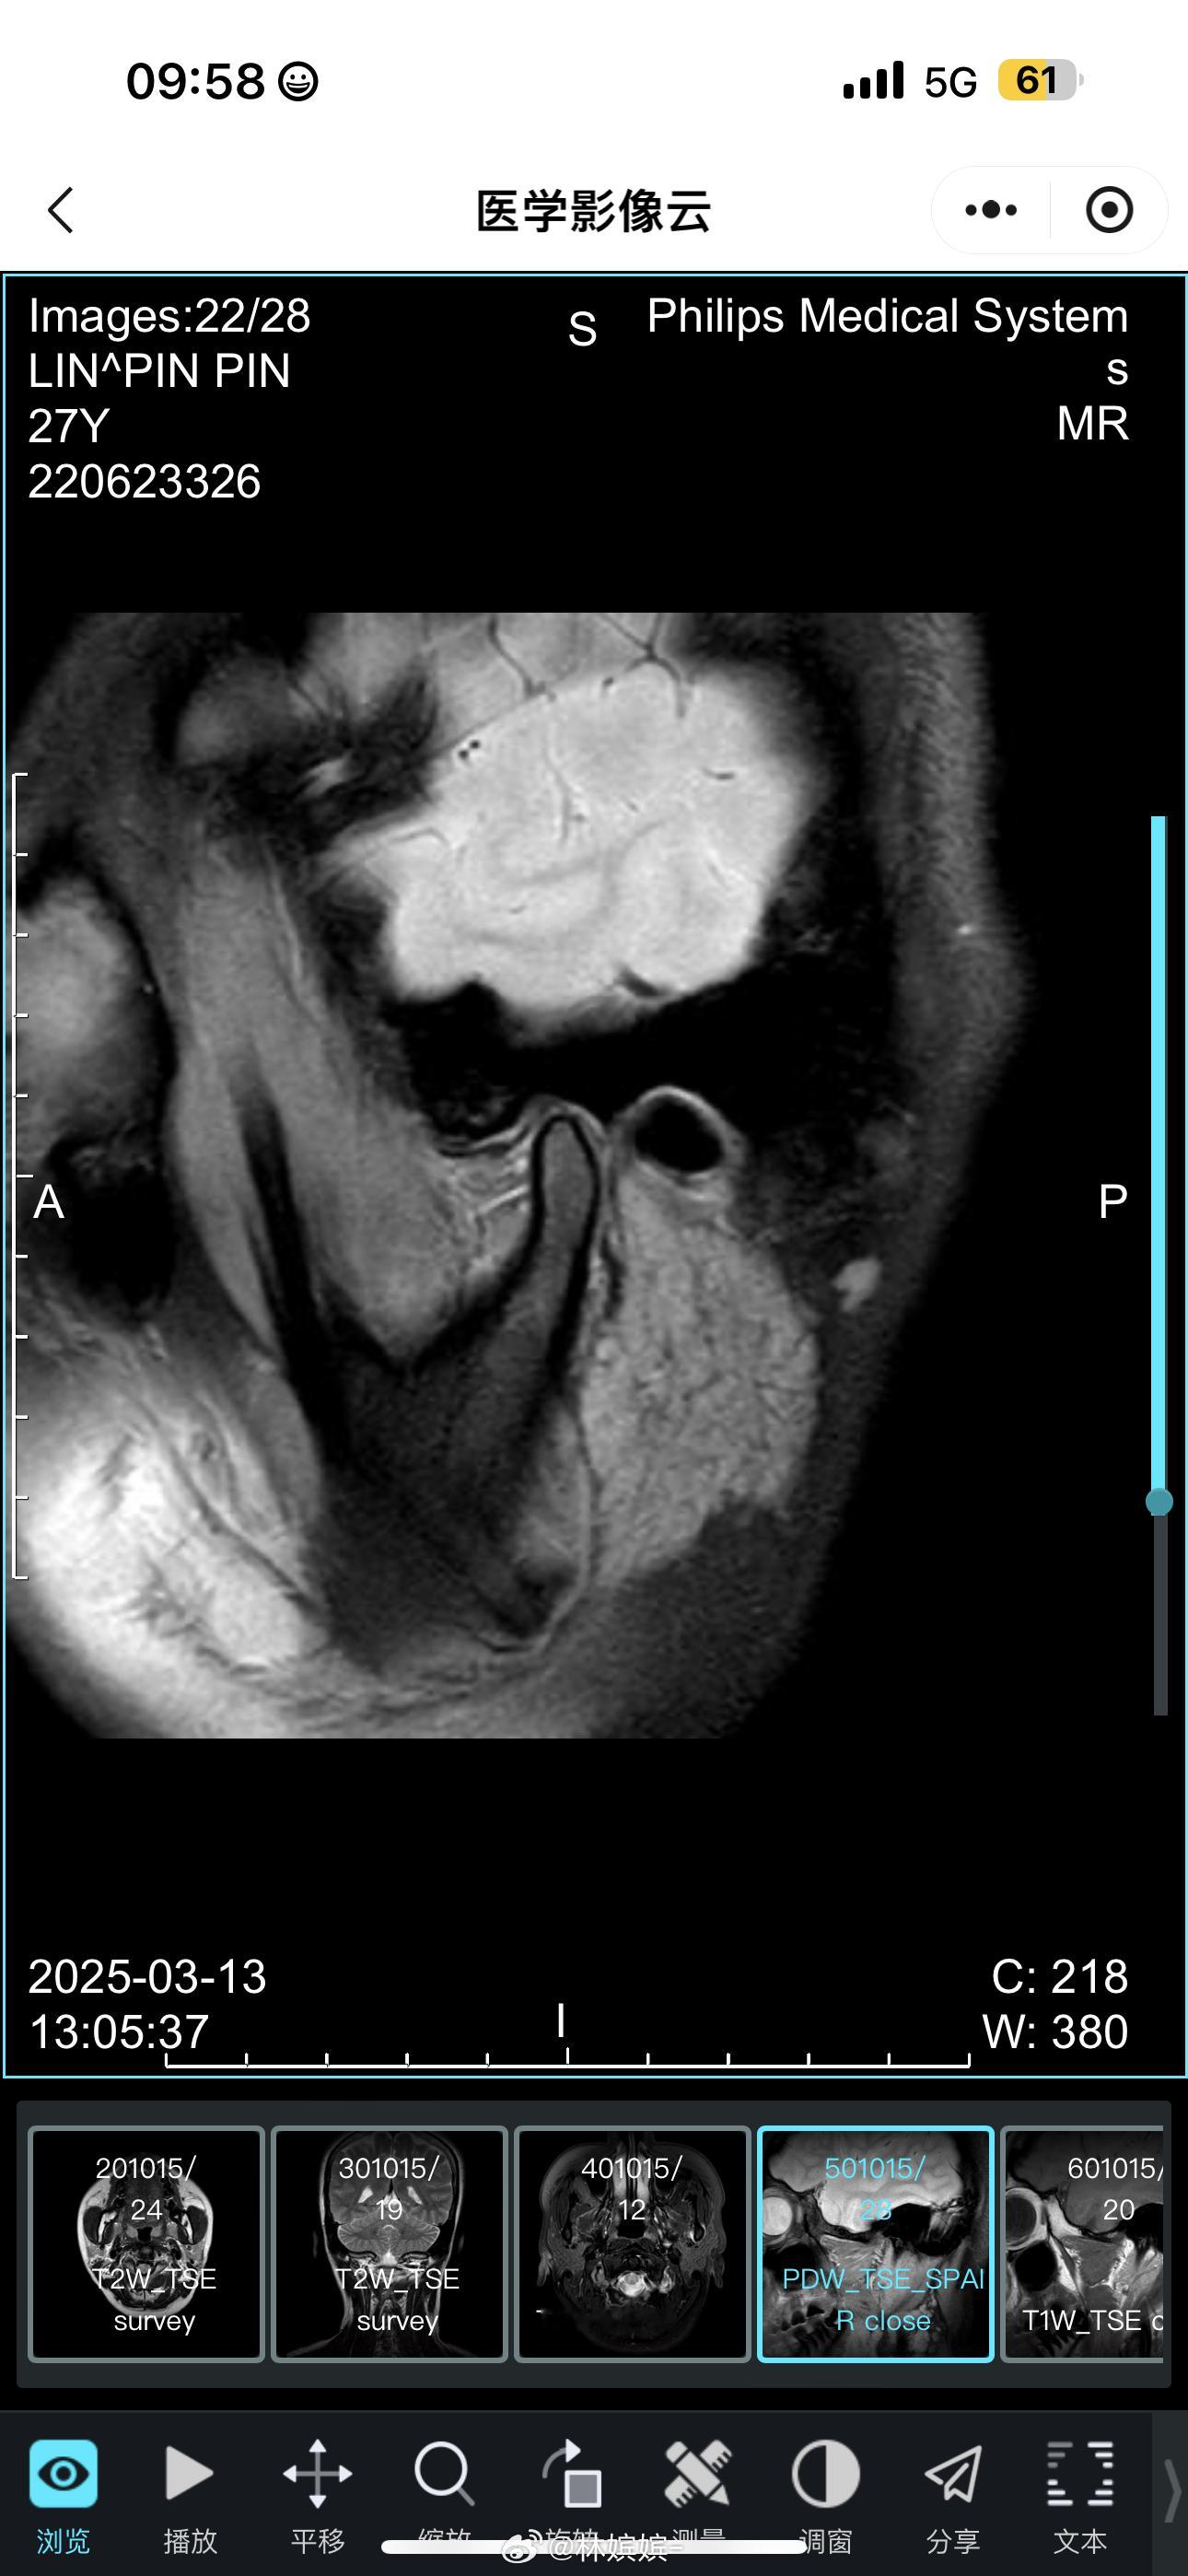

📌25年,因下颌紊乱到口腔医院做了颞下颌关节检查后,开始左侧严重头痛,怀疑在检查过程中引起炎症压迫神经。3月复查,做了颞下颌关节核磁共振发现左侧有积液和水肿,确认下颌关节左侧有炎症,初步判断是此原因导致的阶段性偏头痛。在注射玻璃酸钠及佩戴咬合器后,有所改善。